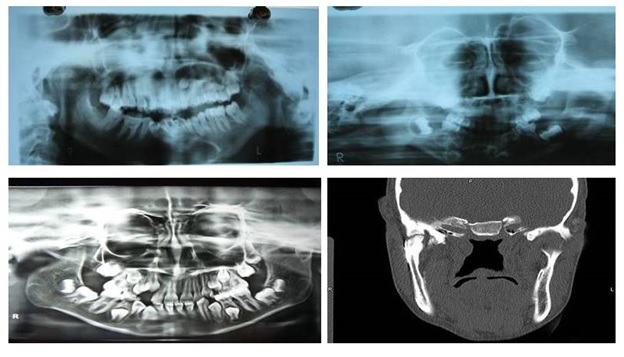

Total 10 patients with Temporomandibular Joint (TMJ) ankylosis reporting to the outpatient department of Oral and Maxillofacial Surgery, Maharaja Ganga Singh Dental College and Research Centre, Sri ganganagar, Rajasthan, India were included irrespective of age, sex, caste and socioeconomical status. Diagnosis of TMJ ankylosis was based on the basis of clinical assessment as Maximum inter-incisal Mouth Opening (MMO) [Table/Fig-1] and other cardinal signs of ankylosis [1] followed by radiographic assessment using Postero-anterior (PA) mandible view, Orthopantomogram (OPG), lateral oblique view and CT scan which showed various degrees of condylar involvement with condyles varying from normal size to a large spherical mass involving the condylar process as well as the coronoid process [Table/Fig-2].

Results: A total of 10 patients with TMJ ankylosis were successfully treated by interpositional gap arthroplasty. Mean age of the patients was 8.6 years. All the patients had a history of trauma to the TMJ which could be the aetiological factor for TMJ ankylosis. Patients had pre-operative maximal mouth opening at incisal edges of 1-11mm, (mean 6.8mm). Patients had maximum mouth opening of 30-38mm (mean 34.5mm) on last follow-up (mean 4.1 years). Transient paraesthesia of the temporal branch of facial nerve was observed in 1 case which was recovered within 3 months by conservative treatment. Periodic OPGs were obtained to check the maintenance of the intra-articular space [Table/Fig-10]. There were no signs of recurrence in any patients up to last follow-up visit [Table/Fig-11]. Overall results of all the cases have been described in [Table/Fig-12].

Post-operative X-rays show no signs of recurrence.